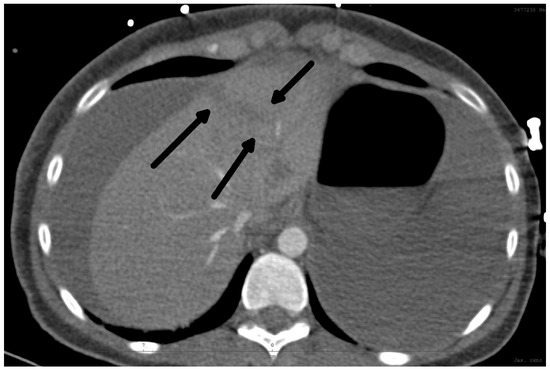

Rare Complication of Cardiopulmonary Resuscitation—Liver Injury

by David Hoskovec, Pavol Klobušický, Adam Pudlač, Matyáš Lochman, Zdeněk Krška and Petr Dytrych

Medicina 2024, 60(9), 1470; https://doi.org/10.3390/medicina60091470 - 9 Sep 2024

Background and Objectives: Liver injury is a rare complication of cardiopulmonary resuscitation. Correct and early diagnosis and treatment are essential. The clinical signs of injury may be masked by the cardiac arrest. We present a single-centre retrospective observational study of traumatic liver [...] Read more.

Background and Objectives: Liver injury is a rare complication of cardiopulmonary resuscitation. Correct and early diagnosis and treatment are essential. The clinical signs of injury may be masked by the cardiac arrest. We present a single-centre retrospective observational study of traumatic liver injury after cardiopulmonary resuscitation. Materials and Methods: A retrospective analysis of the patients treated for liver injury after cardiopulmonary resuscitation was conducted. Demographic data, the cause of resuscitation, the duration of restoration of spontaneous circulation (ROSC), and the surgical approach were analysed. Results: We have treated nine patients with severe liver injury after cardiopulmonary resuscitation. The diagnosis was made on the basis of cardiopulmonary instability, a fall in the erythrocyte count in eight cases, and was confirmed by CT or ultrasound examination. The last one was diagnosed accidentally on MR. Surgery, in cases of unstable patients, was followed immediately after a diagnosis. We combined liver sutures and intra-abdominal packing with a planned second-look surgery. Five of the nine patients survived. Conclusions: Liver injury after cardiopulmonary resuscitation is rare and is associated with high mortality. The recurrence of cardiopulmonary instability and/or a low or falling red blood cell count are the main signs of this injury. Bedside ultrasound and CT scans are the most important methods to confirm the diagnosis. The rule of surgical repair is the same as in all liver injuries, regardless of aetiology. The key factors for survival include early diagnosis, together with the length of restoration of spontaneous circulation (ROSC). Full article

Show Figures

Figure 1